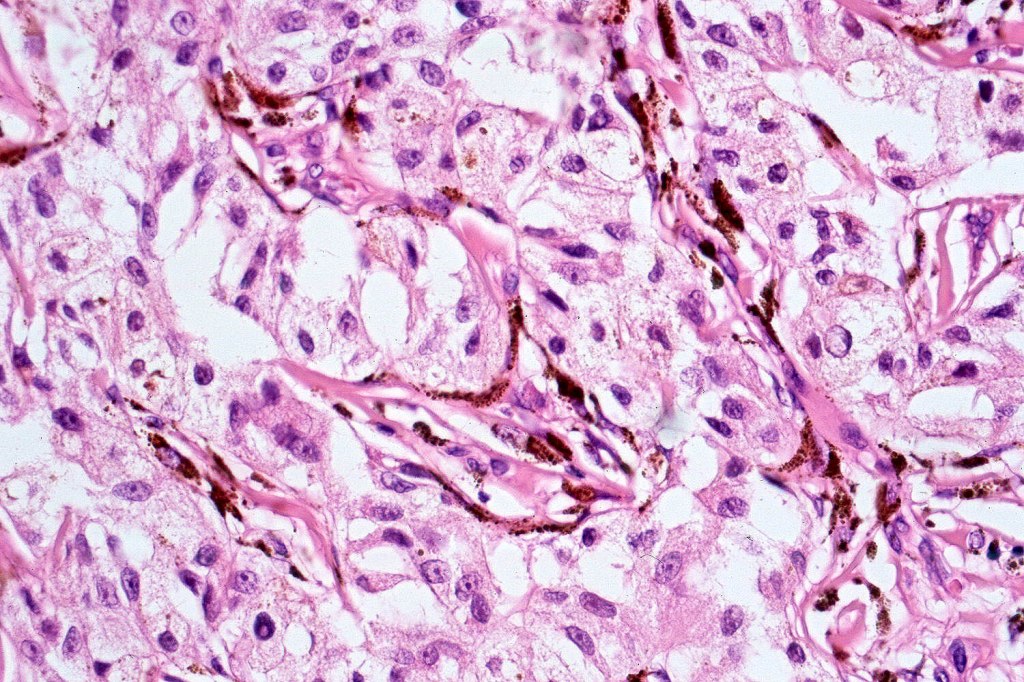

Histologically, it is characterized by a dense population of spindled, dendritic melnanocytes & melanophages with variable fibrosis. It may sometimes represent a component of a combined nevus. Mitotic activity is not usually present and pleomorphism is absent (see atypical blue nevus below). Involvement of the arrector pili muscle is not uncommon.

•Admixture of spindle cells, pigmented bipolar or dendritic cells & melanophages

•Cytoplasm is pale and nuclei are small with inconspicuous nucleoli

•An alveolar pattern is characteristic particularly with clear cell nodules

•Multinucleate giant cells sometimes present

•Stromal fibrosis, myxoid change, vascular hyalinization with cyst formation are often seen

•Some tumors are composed spindle cells in a fascicular or neuronevoid pattern